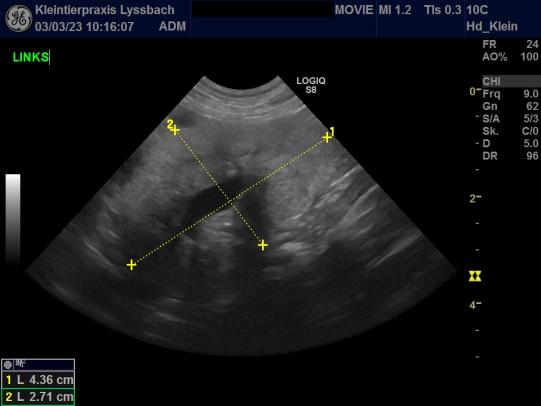

Schon im Alter von knapp 1 1/2 Jahren wurde bei Movie eine Nierenfunktionsstörung festgestellt. Abklärungen deuteten darauf hin, dass sich ihre Nieren wohl nicht korrekt entwickelt hatten (Nierendysplasie). Mit Nierenschonfutter und Medikamenten zur Reduktion des Blut-Phosphorgehaltes zeigte Movie aber bisher abgesehen von der erhöhten Trinkmenge trotz den hohen Nierenwerten eine gute Lebensqualität. Sie zeigte bisher auch keinen durch den Nierenschaden bedingten Bluthochdruck oder übermässigen Eiweissverlust im Urin.